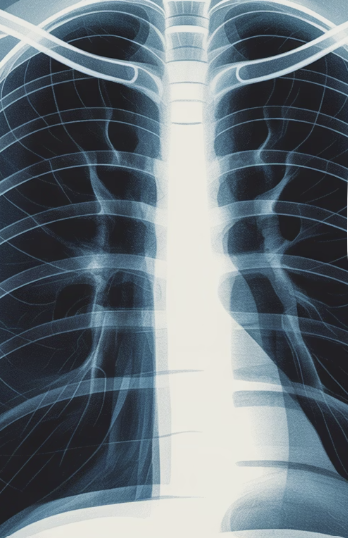

이럴 때는 호흡기내과를 방문해 X-ray 검사나 폐 기능 검사를 받아보는 것이 안전합니다.